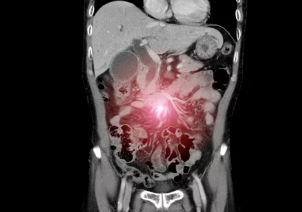

4. 장폐색 & 장유착, 어떻게 진단하나요? 영상 검사와 혈액 검사

장폐색과 장유착은 환자의 증상, 병력, 신체 검사 결과를 종합적으로 고려하여 진단합니다. 복부 X-ray, CT, MRI 등 영상 검사를 통해 장 폐쇄 부위와 원인을 확인하고, 혈액 검사를 통해 염증 수치, 전해질 불균형 등을 확인합니다.

- 복부 X-ray: 장 내 가스 분포를 확인하여 장 폐쇄 여부를 진단합니다.

- CT (컴퓨터 단층촬영): 장 폐쇄 부위와 원인을 더욱 정확하게 확인할 수 있습니다.

- MRI (자기공명영상): CT보다 연부 조직을 더욱 자세히 볼 수 있어 장유착 진단에 유용합니다.